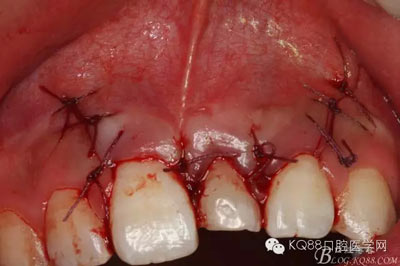

圖18.縫合